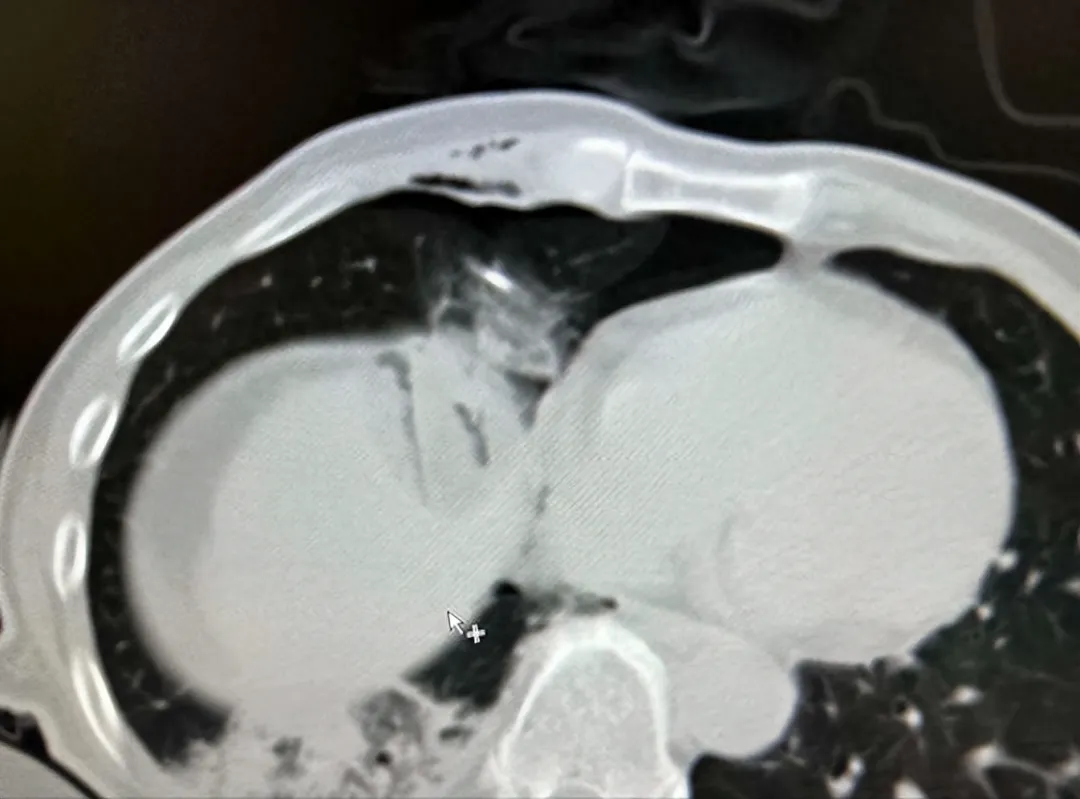

有一位来自福建患者,五年前曾因右肺结节接受了手术切除术。后来左肺又长新的结节,二次手术创伤大,于是患者选择了射波刀治疗。可结节反而长大,并紧靠主动脉,如果消融,容易导致消融不完全,并损伤喉返神经。因此,我在消融前进行人工气胸术,将结节跟主动脉隔开,顺利完成结节的冷冻消融。

在消融前建立人工气胸,通过空气隔离的技术消除消融如邻近纵隔、心脏及大血管的胸部肿瘤以及邻近膈肌的肝顶部肿瘤等盲区,形成足够的安全穿刺空间,以便顺利完成肿瘤的完全消融治疗。同时,在影像技术引导下具有定位精确、图像整体性好及显示穿刺针、进针路径、肿瘤与瘤旁脏器关系的优势,能够为患者提高完全消融率及有效减少并发症发生。

注入500ml气体(最好是CO2),建立人工气胸将肺与膈肌分离开;

冷冻消融清晰显示足够的消融范围;

通过导管抽出气体,肺复张,人工气胸消除;

▲利用肝导向入路seldinger技术,在人工气胸下行膈顶肝癌冷冻消融术。